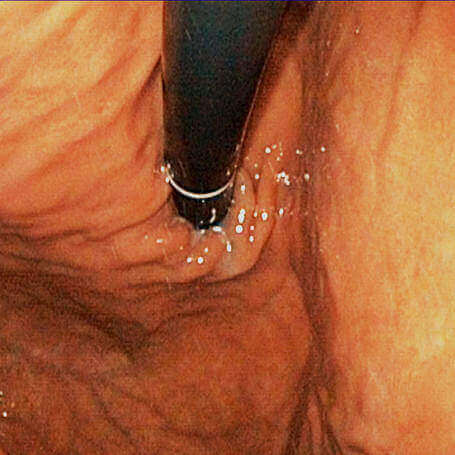

Classificação endoscópica para esofagite Classificação de Los Angeles:

Grau A – Uma ou mais soluções de continuidade da mucosa, não maiores que 5 mm cada, que não se estendem entre duas pregas longitudinais;

Grau B – Uma ou mais soluções de continuidade da mucosa, com mais de 5 mm cada, não contíguas entre o topo de duas pregas longitudinais;